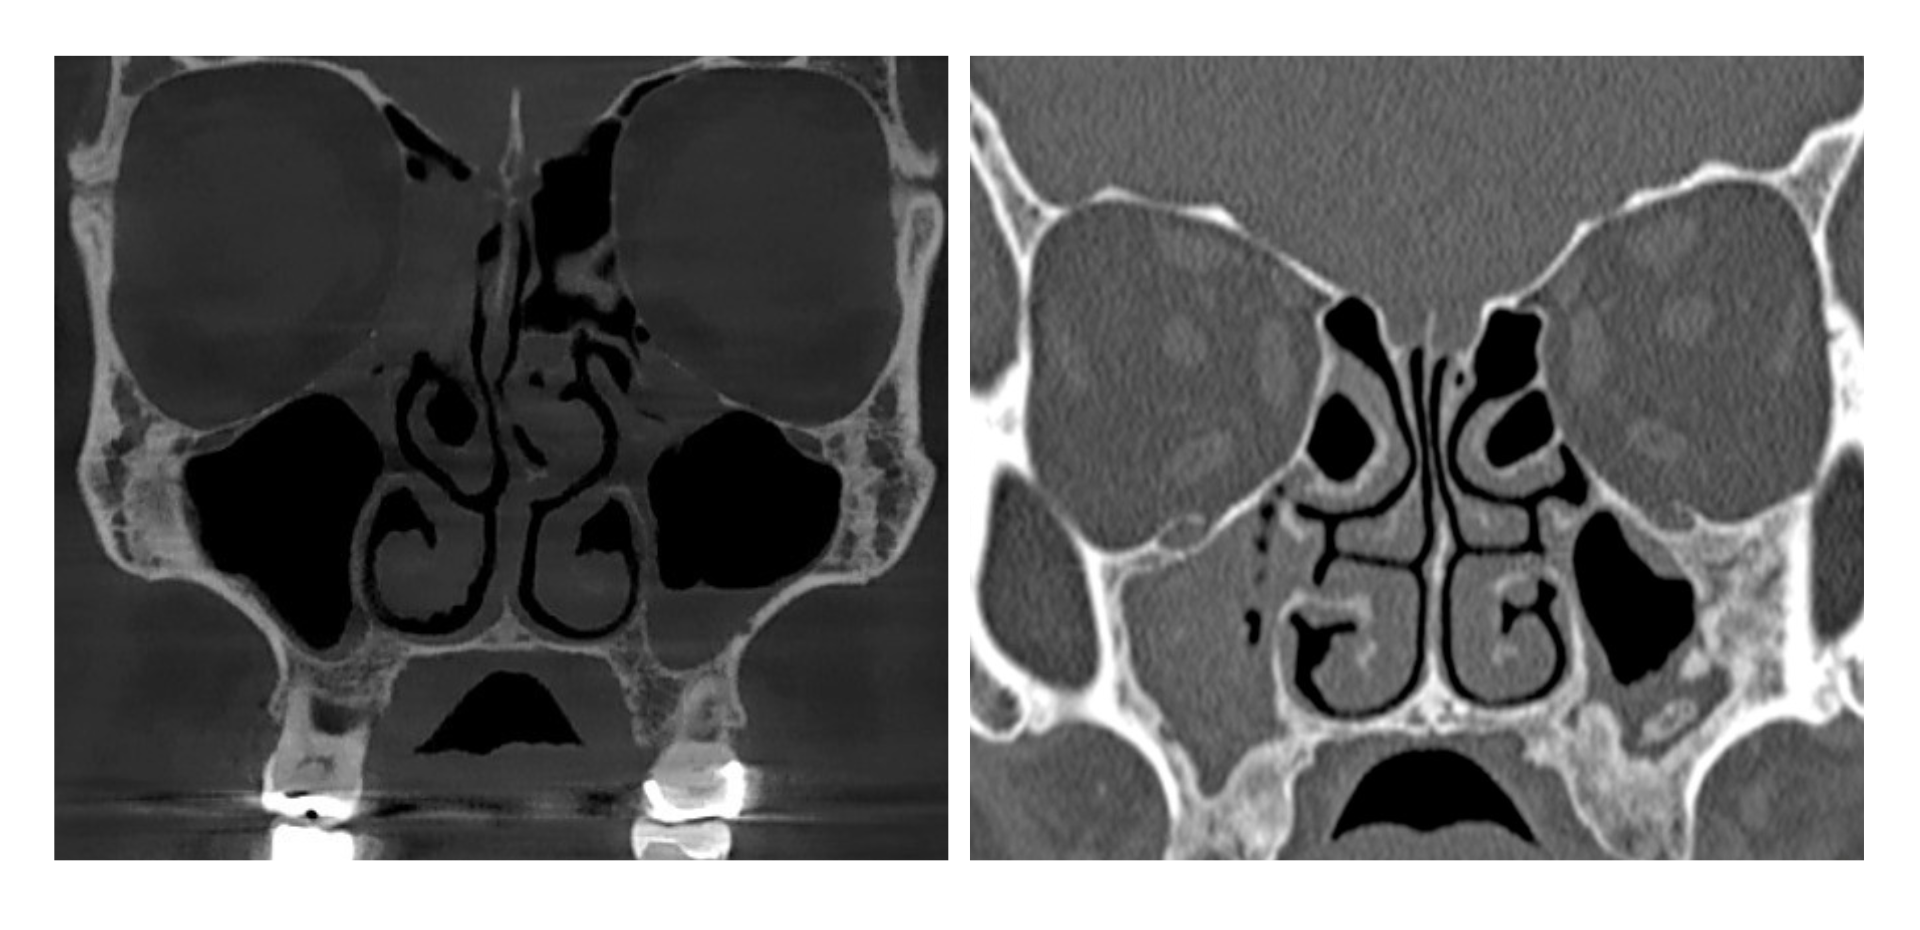

- Evaluar senos paranasales y diferenciar patología odontogénica y no odontogénica.

Senos Paranasales (CBCT) -  Dra. Ivana Vitulli

• Fundamentos técnicos del estudio sinusal en CBCT.

• Anatomía funcional y variantes anatómicas.

• Sinusitis maxilar de origen odontogénico.

• Evaluación diagnóstica preoperatoria.

• Análisis de casos clínicos anonimizados y entrenamiento en redacción de informes con finalidad docente